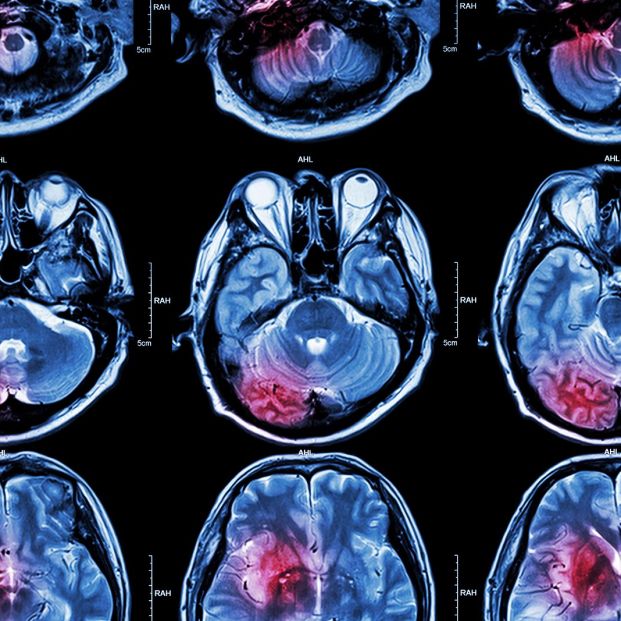

Investigadores del Hospital General de Massachusetts (Mass General Brigham) han desarrollado un nuevo y robusto modelo de inteligencia artificial (IA) capaz de analizar conjuntos de datos de resonancia magnética cerebral para realizar numerosas tareas médicas, como identificar la edad cerebral, predecir el riesgo de demencia, detectar mutaciones en tumores cerebrales y predecir la supervivencia al cáncer cerebral.

Para abordar estas limitaciones, el equipo de investigación diseñó un núcleo adaptativo de imágenes cerebrales, o BrainIAC. La herramienta utiliza un método llamado aprendizaje autosupervisado para identificar características inherentes de conjuntos de datos sin etiquetar, que posteriormente pueden adaptarse a diversas aplicaciones. Tras preentrenar el marco con múltiples conjuntos de datos de imágenes de resonancia magnética cerebral, los investigadores validaron su rendimiento en 48.965 exploraciones de resonancia magnética cerebral diversas en siete tareas distintas de diversa complejidad clínica.

Descubrieron que BrainIAC podía generalizar con éxito sus aprendizajes en imágenes sanas y anormales y, posteriormente, aplicarlos tanto a tareas relativamente sencillas, como la clasificación de tipos de resonancia magnética, como a tareas muy complejas o la detección de tipos de mutaciones en tumores cerebrales. El modelo también superó a tres marcos de IA más convencionales y específicos para cada tarea en estas y otras aplicaciones.